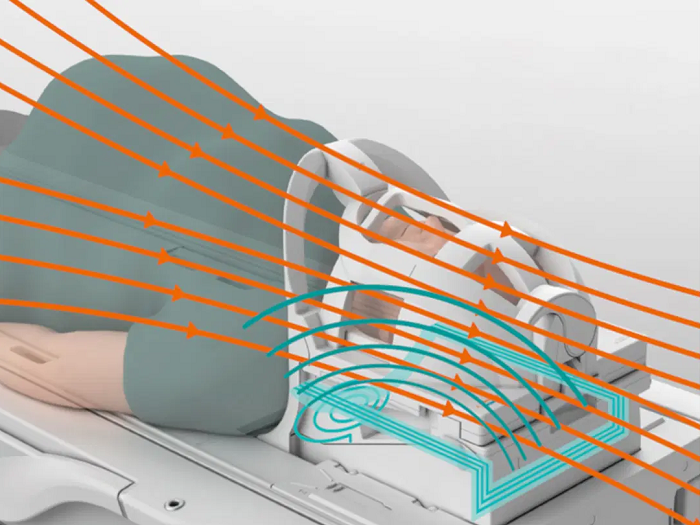

BioMatrix Sensors. New ultra-high density BioMatrix coils utilize seamlessly integrated respiratory sensors to acquire and display the patient’s respiration. Image Credit: Siemens Healthineers.

BioMatrix Sensors — Anticipate motion for high-quality results

BioMatrix Sensors, fully incorporated into the system architecture, capture respiratory and cardiac3 motion, improving consistency and freeing up the user to choose the optimal exam approach. This pairing guarantee high-quality outcomes.

BioMatrix respiratory sensor

Respiratory triggering is possible without using a navigator tup or a breathing belt.